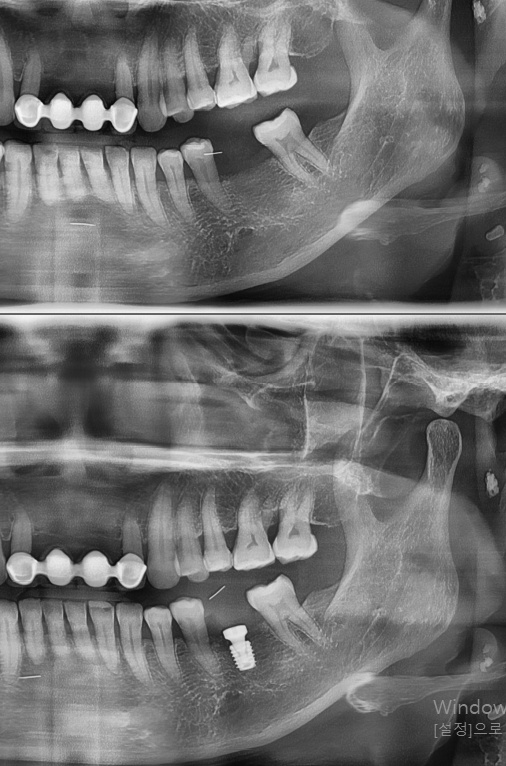

상기 환자 치아를 상실하고 난 후

발치 당시 뼈의 양과 질이 매우 BAD 하여

뼈이식을 진행하고 6개월 정도 충분이 기다렸습니다.

충분한 뼈가 생성됨을 확인 한 후

간단한 임플란트 식립을 진행하였습니다.

보철 시기는 8주 뒤로 예상하고 있습니다.

수술 시간은 3분이었습니다.